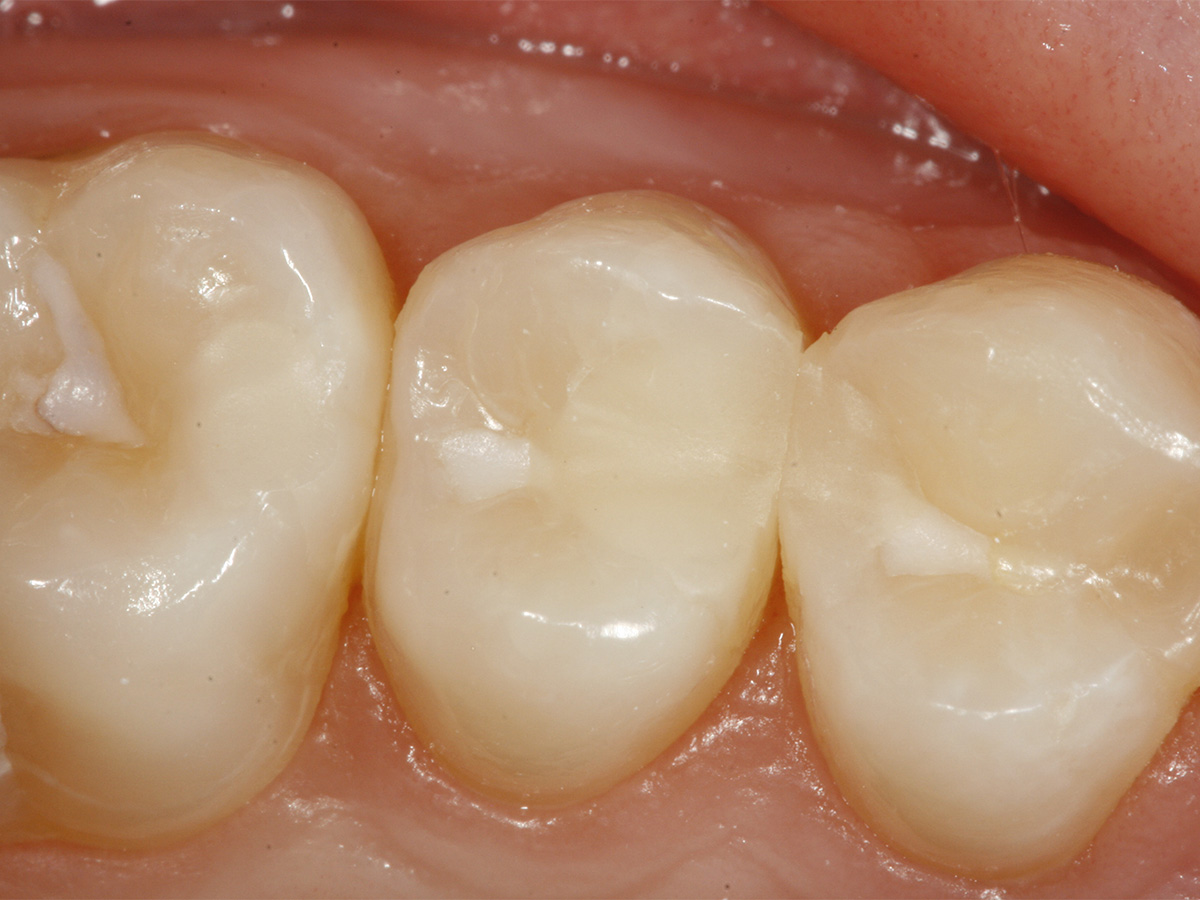

Abbildung 1

Aufnahme bei Erstuntersuchung.